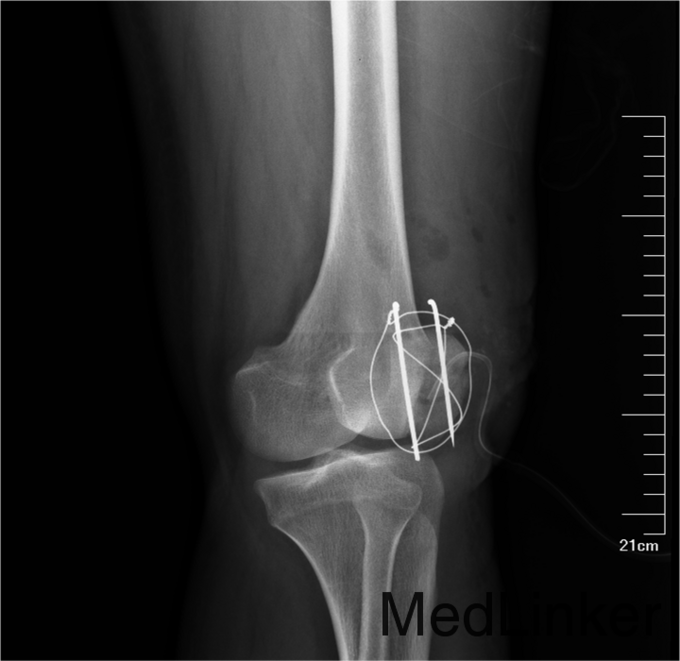

患者入院后急诊行左髌骨清创缝合术,左髌骨骨折切开复位张力带内固定术。术后局部换药无红肿渗出,冷敷,甘露醇消肿,患肢抬高。患者术后14无不良主诉给予拆线。